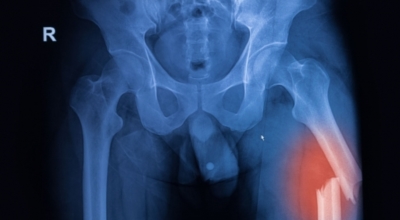

고관절이란 골반을 지탱하는 관절로서 근육과 힘줄로 구성되어 있어요. 학계에서는 고관절을 엉덩이 관절이라고 부르기도 하며 인체의 하중을 지탱하는 아주 중요한 관절입니다. 각별히 고관절은 우리가 정상적으로 서있거나 움직일 수 있게 만들어주며 달리기, 점프, 무거운 무게를 들 때 최대 체중의 2~10배 가량의 하중을 받기 때문에 적절한 관리가 필요합니다. 오늘은 고관절에서 일어날 수 있는 고관절 통증 증상에 관해서 알려드리도록 하겠습니다.

고관절염은 고관절에 나타나는 관절염을 말하며 고관절의 연골이 닳게 되면서 뼈와 뼈가 서로 부딪히며 통증을 일으키게 돼요. 고관절염 초기 증상으로는 사타구니 부위가 불편하게 느껴지며, 무리하면 통증이 발생할 수 있으며, 관절염 증상이 심해지면서 사타구니에서 느끼던 통증이 허벅지와 엉덩이 통증으로 이어지기도 하는데, 고관절염 통증 증상으로 초기에는 허리 통증이 나타나 허리 질환과 혼동하기 쉬우며 각별히 척추질환이 있는 사람은 고관절 통증과 마찬가지로 엉덩이, 다리 통증이 동반되기 때문에 훨씬 헷갈리는 경우가 많습니다.

각별히 젊은 남성에게 잘 발생하며 엉덩이와 골반 주위에 뻐근한 통증이 동반되며 정상적인 보행이 되지 않고 절뚝거리는 증상이 나타난다면 대퇴골두 무혈성 괴사일 가능성이 있답니다. 이 증상은 괴사 부위의 골절이 발생되어 고관절 손상으로 이어지면 발생하는 증상으로 아직까지 정확한 원인은 규명하기 힘드나 과음이나 고지혈증, 스테로이드 과남용이 영향을 줄 수 있어요.